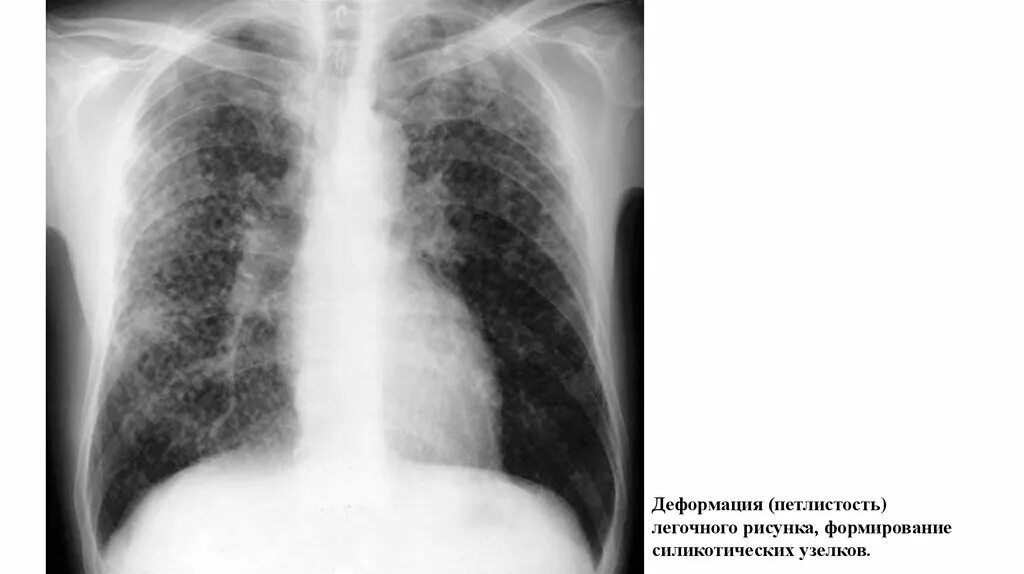

Аортокоронаросклероз легких что это такое